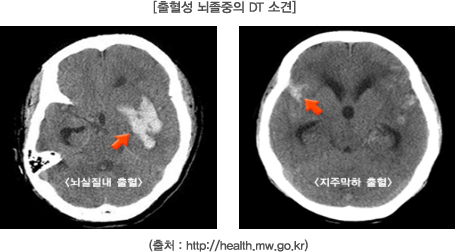

급성 허혈성 뇌졸중이 발생하였다면 혈전용해제와 정확한 뇌 영상은 뇌졸중의 진단과 치료에 있어 중요한 역할을 합니다. 조영제를 쓰지 않는 두부 전산화 단층촬영(CT)은 급성 신경학적 결손의 원인인 출혈성 뇌졸중을 감별하는데 사용되지만 뇌졸중에서 나타나는 세포의 변화는 두부 전산화 단층촬영에서 정확하게 확인할 수 없습니다. 자기공명영상(Magnetic resonance imaging, MRI)은 증상 발생후 8~12시간까지는 경색이 정확하게 나타나지 않기 때문에, 급성 허혈성 뇌졸중을 진단하는데 있어서 제한점이 있습니다. 따라서 민감도가 크고 해부학 해상도가 높은 자기공명영상 기법 중 확산 가중 영상(Diffusion-Weighted Imaging : DWI)과 관류영상(Perfusion Imaging : PI)을 사용하여 허혈성 뇌졸중을 진단하고 치료함으로써 임상적 성과가 향상되었으며, 무엇보다 뇌졸중을 조기에 발견하고 특성화를 가능하게 합니다.

CT는 뇌졸중 진단을 위해 가장 흔히 사용하는 검사법으로 X-선을 이용하여 다양한 각도에서 신체를 촬영하고 컴퓨터를 이용하여 신체의 단면 영상을 만들어 내는 것입니다.이 검사방법의 장점은 비교적 빠른 시간에 검사를 진행할 수 있으며 뇌출혈 여부를 신속히 감별할 수 있습니다. 그러나 뇌종양이 뇌출혈처럼 보이는 경우도 있고, 허혈성 뇌졸중의 경우 발병 후 일정한 시간이 지나야 병변이 보이므로 진단에 어려움을 주기도 합니다. 출혈성 뇌졸중의 경우 출혈 발생 후 즉시 CT에서 관찰되기 때문에 허혈성 뇌졸중을 치료하기 위한 혈전용해제 사용에 앞서 반드시 뇌출혈을 감별하는 도구로서 유용하게 사용되고 있습니다. 뿐만 아니라 CT촬영은 혈전용해제 사용 이후에 합병증으로 나타날 수 있는 뇌출혈의 발생여부를 경과 관찰하는 데 중요하게 사용되는 검사입니다.